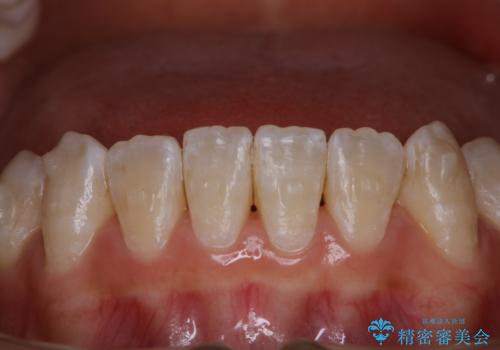

ワイヤー矯正終了時に装置除去と合わせてPMTC

担当医 歯科衛生士